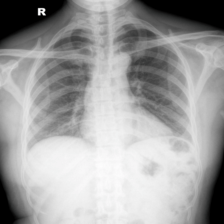

To pre-train a high-performance X-ray foundation model, the first thing we need to do is the collection of large-scale X-ray images. Therefore, a large-scale and high-resolution dataset that contains X-ray medical images is collected for the pre-training. Some representative samples are visualized in Fig. 3.